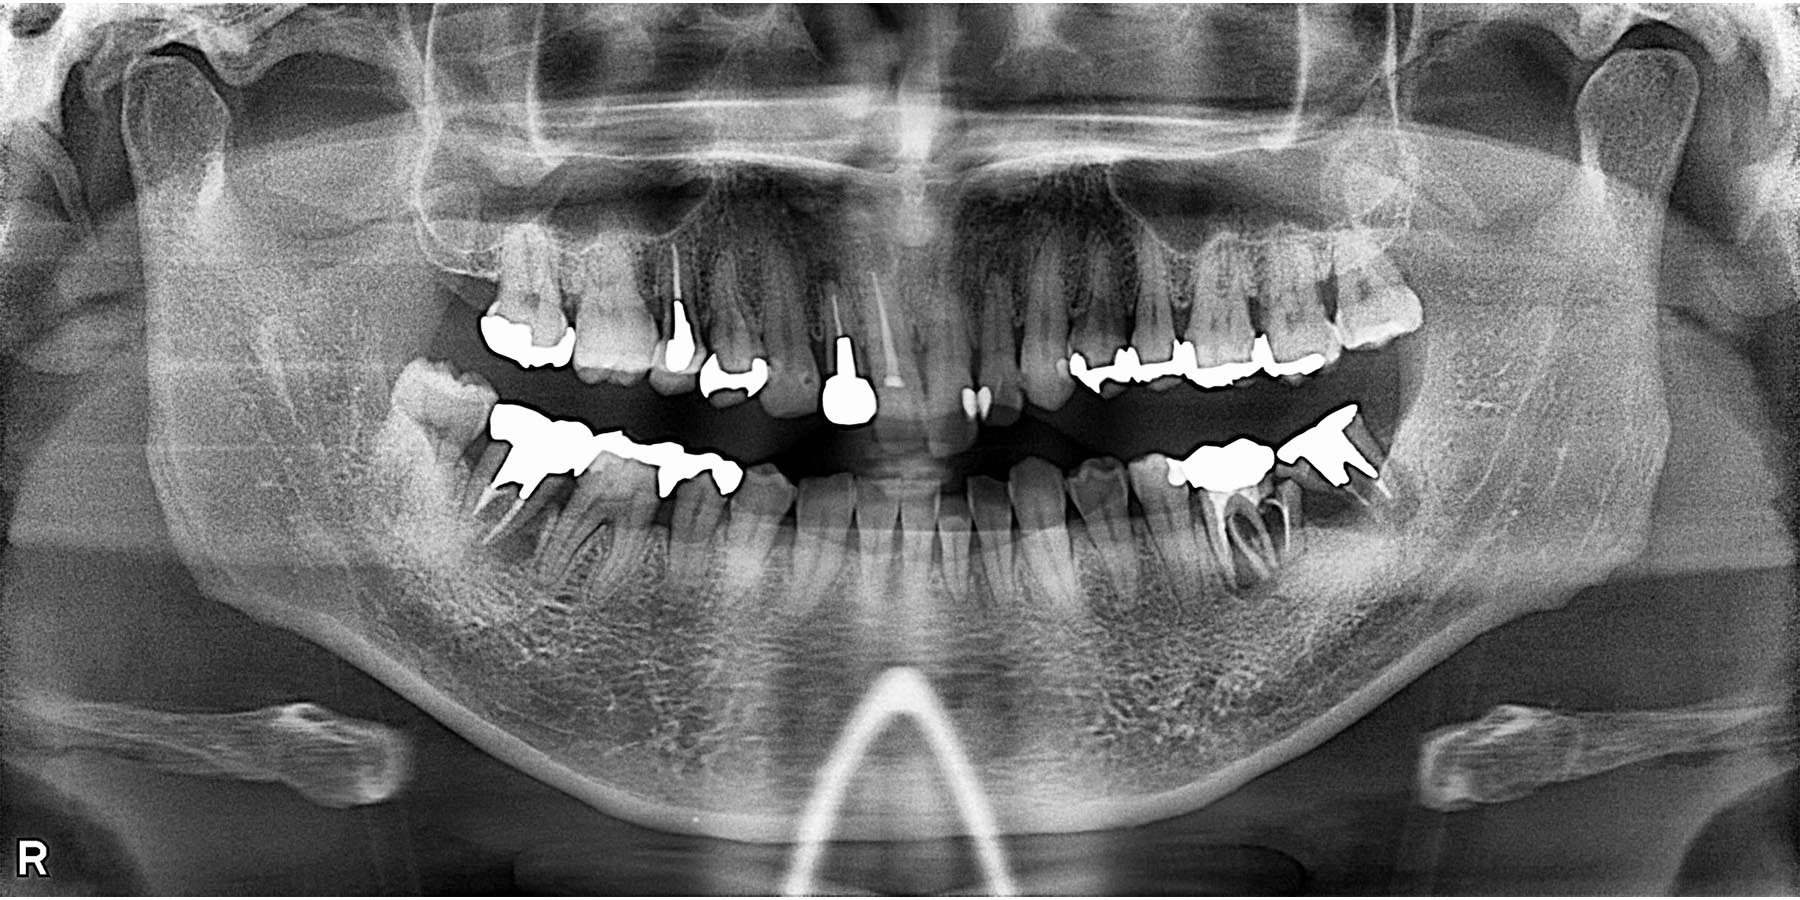

治療前

| 治療内容 | 矯正治療(前歯部) 右下7.左下5.6インプラント治療(3本) 前歯、奥歯セラミック治療(5本) |